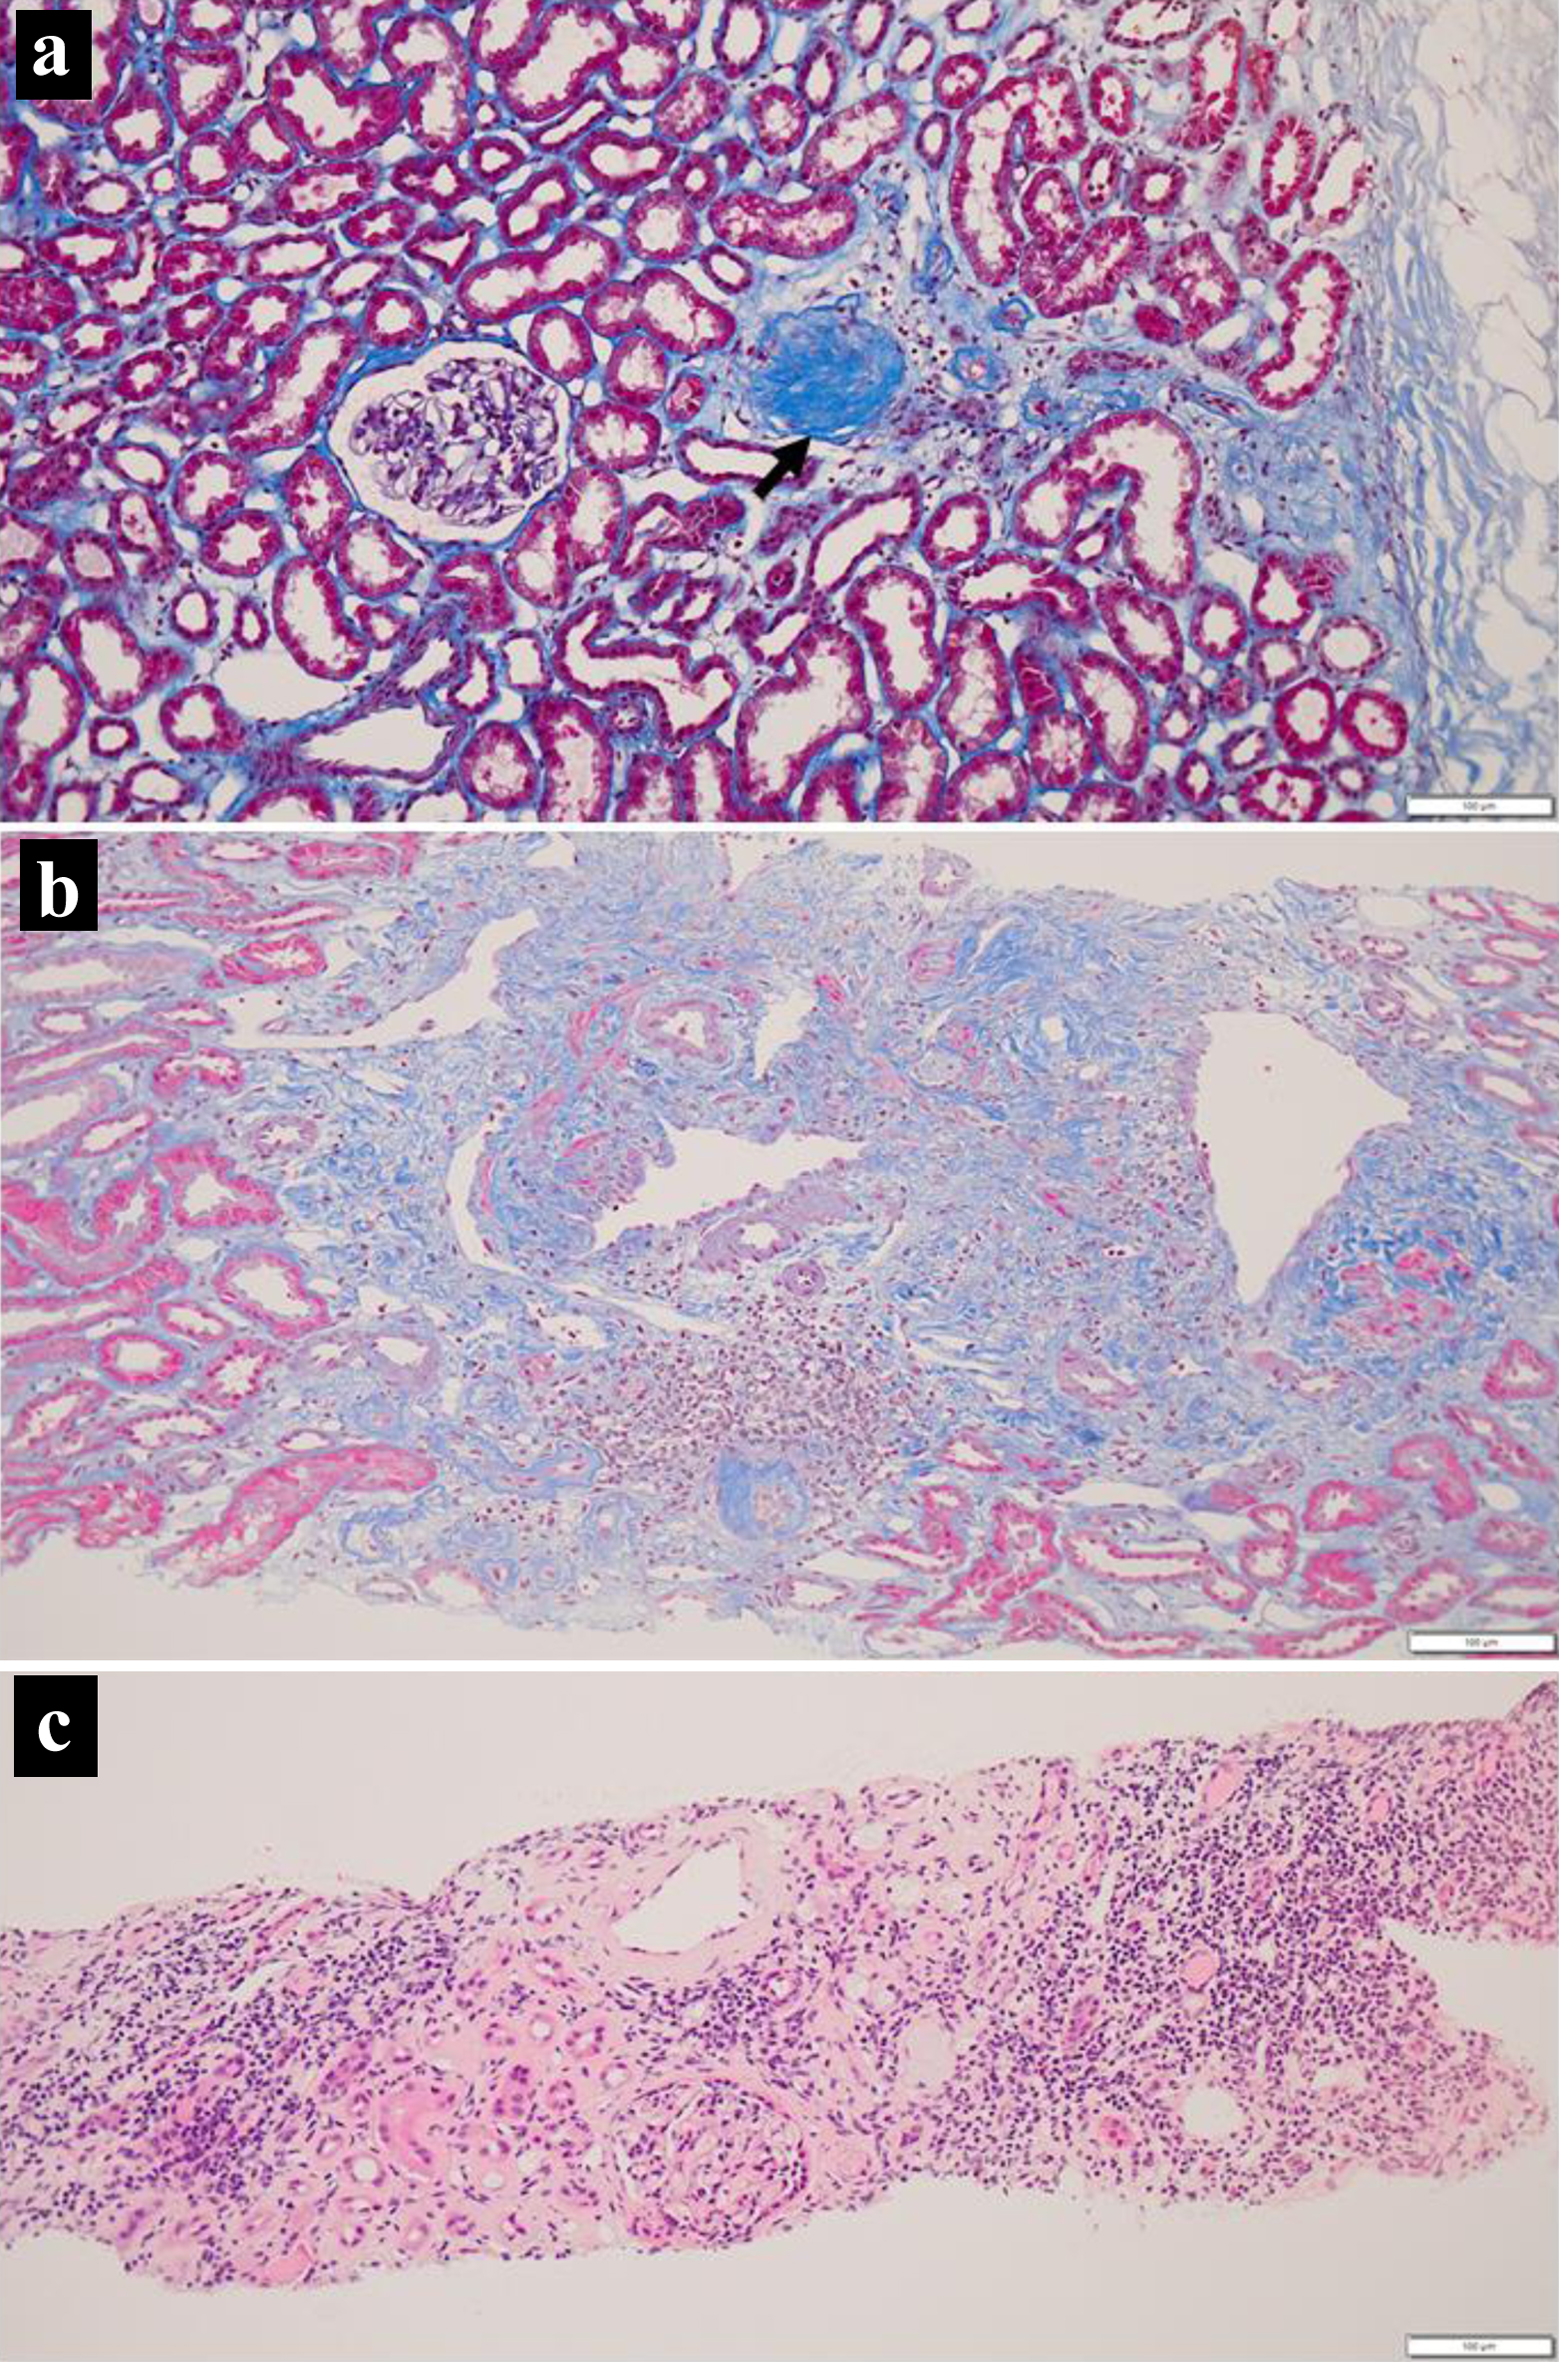

At the age of 19 years, 4 months after the initial visit, she received an ABO-compatible living-donor kidney transplant from her 46-year-old father after three sessions of hemodialysis. At surgery, biopsy of the donor kidney showed two glomeruli with global sclerosis out of 24 glomeruli examined (Fig. 3a) in association with minimal interstitial fibrosis and lymphocytic infiltration. She began to have extended-release tacrolimus (tacrolimus ER) 4 mg daily and mycophenolate mofetil (MMF) 1,000 mg daily, 5 days before the kidney transplantation. One week after the kidney transplantation, oral prednisolone was increased to 20 mg daily and tacrolimus increased to 10 mg daily. The ureteral stent was removed 4 weeks after the kidney transplantation. According to the standard protocol for kidney transplantation, she underwent biopsy of the transplanted donor kidney to reveal no sign of rejection, no deposition of IgG, IgA, IgM, C3, C1q, C4d, or fibrin, 4 weeks and 14 months after the kidney transplantation. In the pathological findings, one glomerulus showed global sclerosis out of 13 glomeruli examined, in association with interstitial fibrosis and lymphocytic infiltration at 4 weeks (Fig. 3b), while 12 examined glomeruli were normal in association with interstitial fibrosis and lymphocytic infiltration as well as renal tubular atrophy at 14 months (Fig. 3c). Computed tomography scans in 8 months showed the kidney transplant in the normal dimension as well as her own kidneys in marked atrophy (Fig. 2c, d).

Click for large image

Figure 3. Kidney biopsy at surgery (a), 4 weeks (b) and 14 months (c) after transplantation. Note one glomerulus with global sclerosis (arrow, a) and interstitial fibrosis with lymphocytic infiltration. Also note more advanced interstitial fibrosis with lymphocytic infiltration at 14 months (c). Masson trichrome stain in a and b, hematoxylin-eosin stain in c. Scale bar = 100 µm.

The prognosis for kidney transplantation in patients with juvenile nephronophthisis was reported to be favorable even in living-donor transplant recipients [12]. Hereditary kidney diseases in autosomal recessive trait such as nephronophthisis are not the contraindication to living-donor transplantation from the families [13]. It is the standard protocol to check by biopsy a pathological sign of rejection in the transplanted donor kidney, 1 month and 1 year after the kidney transplantation. It should be noted in the present patient to observe the limited extent of global glomerulosclerosis and interstitial fibrosis with lymphocytic infiltration in specimens of the donor kidney from her father. A limited number of global glomerulosclerosis in the donor kidney would be the manifestation of the normal aging process in the 46-year-old father [14]. In contrast, lymphocytic infiltration with interstitial fibrosis is against the typical scene of rejection which shows the infiltration of lymphocytes around tubular epitheliums with HLA class II expression. Under the circumstances, global glomerulosclerosis with interstitial fibrosis and lymphocytic infiltration in the donor kidney might be a milder presentation of nephronophthisis with recessive traits [5, 6]. This reasoning remains speculative since genetic testing was not done in the patient and the parents, based on their wishes.